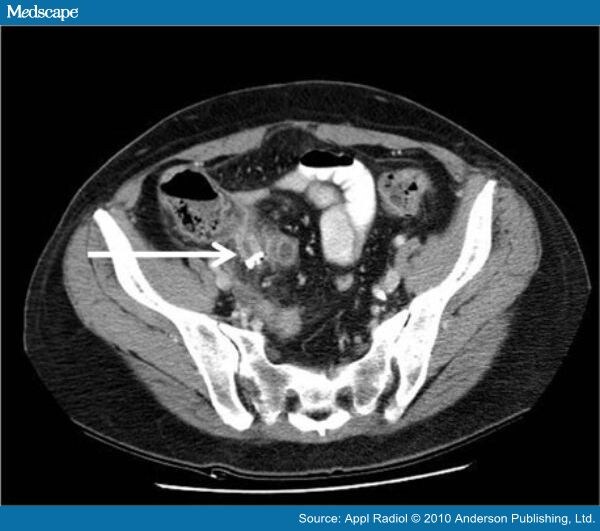

From www.medscape.com

Stump Appendicitis What Is The Appendicular Stump  It is seen following both open and.   stump appendicitis is a rare, delayed complication of appendectomy.   closure of the appendiceal stump is a key step performed during.   stump appendicitis is a rare complication whose incidence is increasing since the advent of laparoscopy.   stump appendicitis has a characteristic ct appearance and may occur within the first year. What Is The Appendicular Stump.